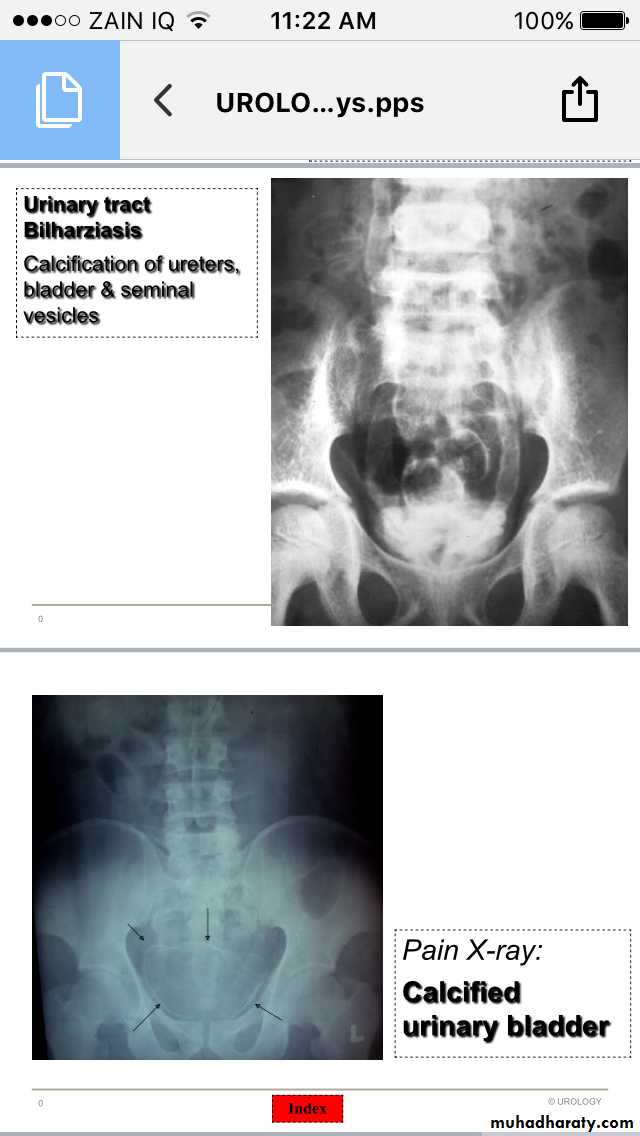

Urinary Bilharziasis

Bilharzial calcification